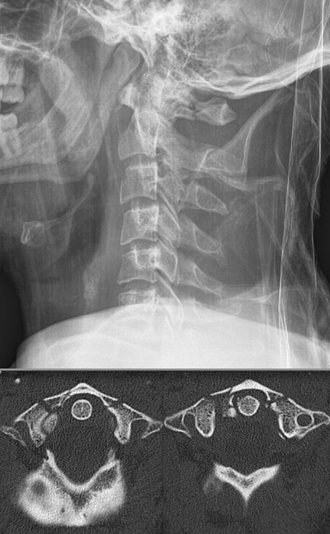

(5) Anderson 骨折

又名齿状突骨折。1 型为齿突尖骨折。是由于翼状韧带及齿突尖韧带牵拉所致。2 型骨折为齿状突腰部的骨折,骨折线一般位于齿突和枢椎椎体交界处。3 型为骨折线下延至枢椎的椎体骨松质。也可延至枢椎侧块。实际上是经枢椎椎体的骨折。